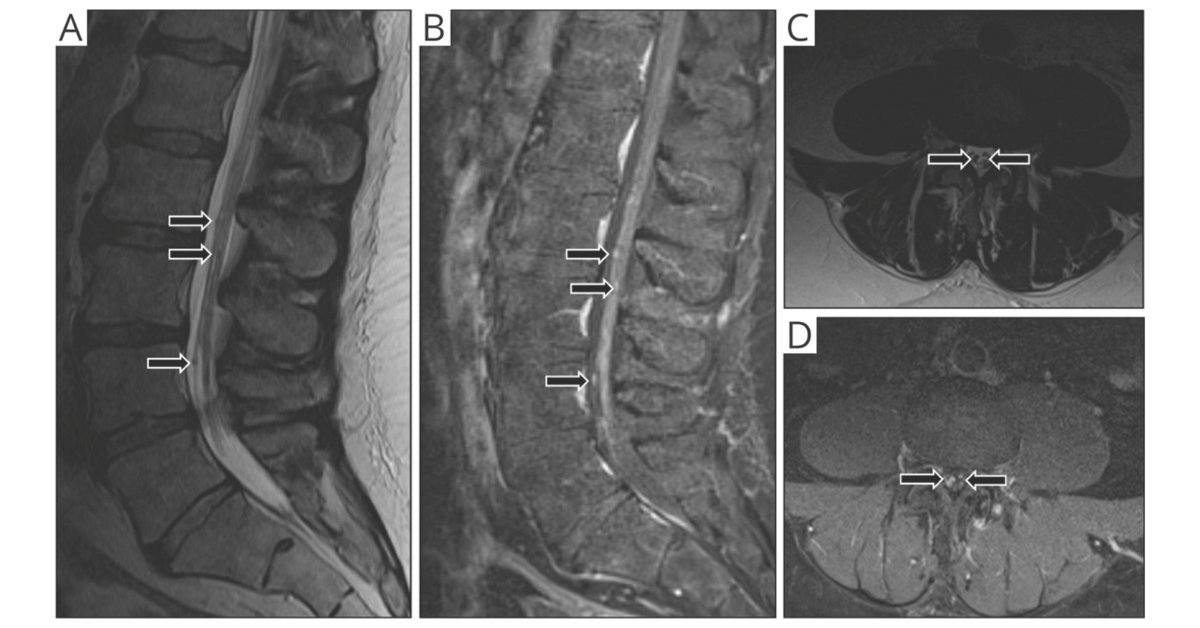

Really great work by Emory Neurology Residency’s Gabriela Bou, MD exploring how neurosarcoidosis affects the cauda equina. Another strong step forward in understanding that not all NS phenotypes are the same. nn.neurology.org/content/9/4/e1…

Thanks for sharing Neurology Journal! #Neurosarcoidosis of the cauda equina often causes nodular enhancement, occurs along with myelitis, and can be challenging to effectively treat. Carolina GS Gabriela Bou, MD Emory Neurology Residency #Sarcoidosis

ICYMI check out our paper on neurosarcodosis of the cauda equina Spencer Hutto, MD Gabriela Bou, MD